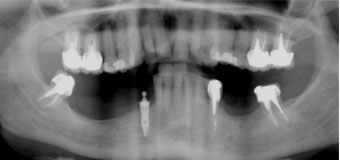

J’ai des problèmes, je refuse l’appareil mobile.

J’ai une maladie des gencives et mes dents tombent les une après les autres, je refuse un appareil que je serais obligé d’enlever

Solution : on va traiter les dents qui sont récupérables et remplacer les autres par des implants.

Implants multiples pour éviter les bridges et redonner des dents individuelles au patient avec traitement d’une maladie parodontale.

Implants multiples pour éviter les bridges et redonner des dents individuelles au patient. État final.